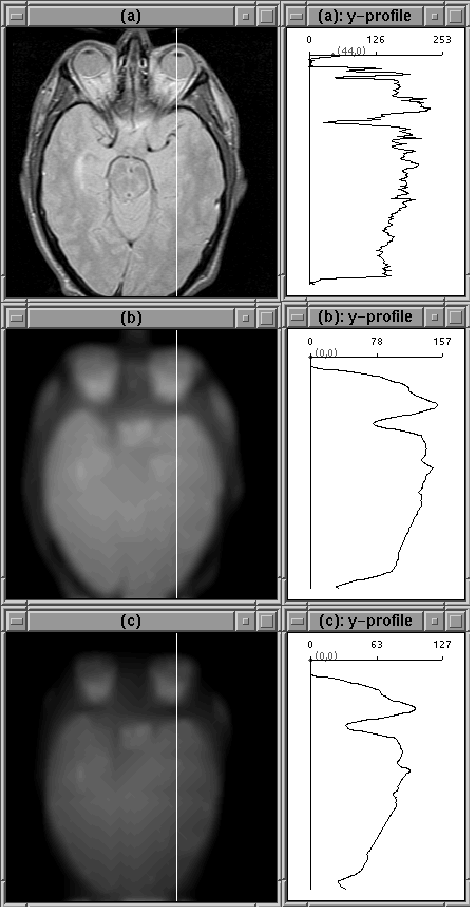

Figure 4.13 shows the same slice used in the previous 2 experiments before and after filtering with the 3D nonlinear anisotropic diffusion filter. The images are similar to the 2D case.

Figure 4.13: Images after 100 iterations of 3D diffusion. (a) Original Image. (b) Diffused image, . (c) Diffused image, .

Figure 4.14 shows the third slice of Data Set 1 before and after 3D diffusion. Filtering appears to have increased the partial volume effect here. Such a characteristic is undesirable since it makes the problem of finding a sharp edge difficult.

Figure 4.14: Images after 100 iterations of 3D diffusion. (a) Original Image. (b) Diffused image, . (c) Diffused image, . The edges of the brain have become unclear due to increased partial volume effects.

3D diffusion filtering is slower than the 2D case and does not seem to offer any advantages for the clinical MR data presented. In fact, 3D filtering appears to worsen the partial volume effect. This result is expected because the data set was acquired as a sequence of 2D slices, not as a 3D volume.